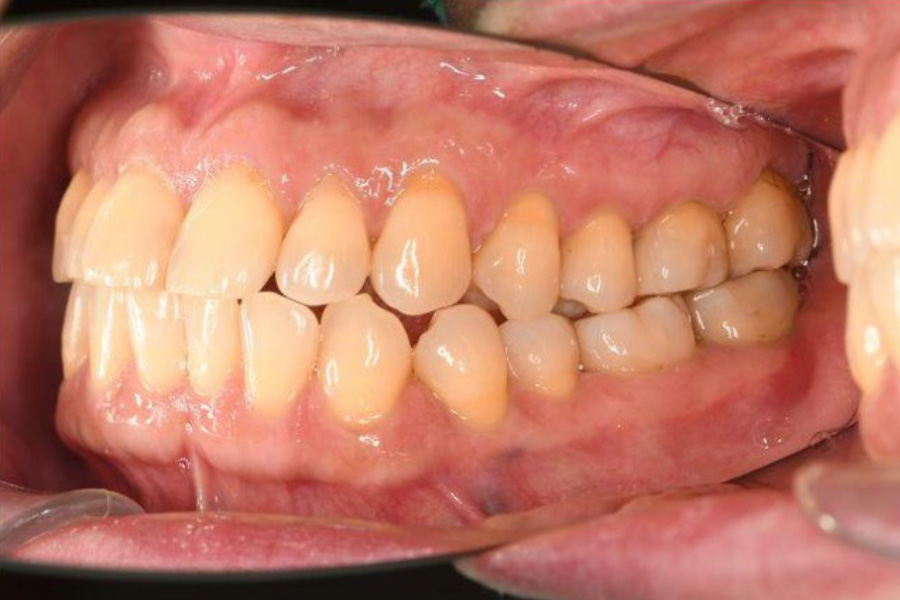

治療後